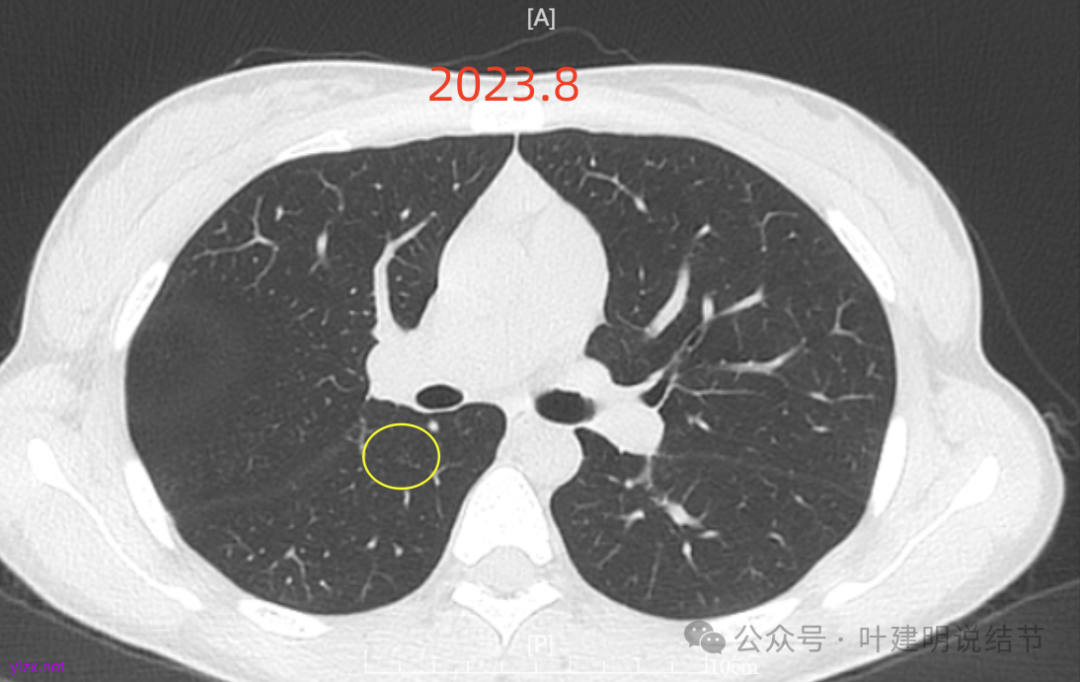

再来看风险最大的病灶6的连续层面:

血管从旁过,没有受结节影响。